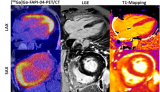

FAPI-PET在分子水平上可视化心肌纤维化

根据一个德国小组的说法,使用成纤维细胞活化蛋白抑制剂(FAPI)放射性示踪剂的PET成像可以在分子水平上可视化心肌纤维化(MF ),并可能成为监测患者的一种新的诊断选择。